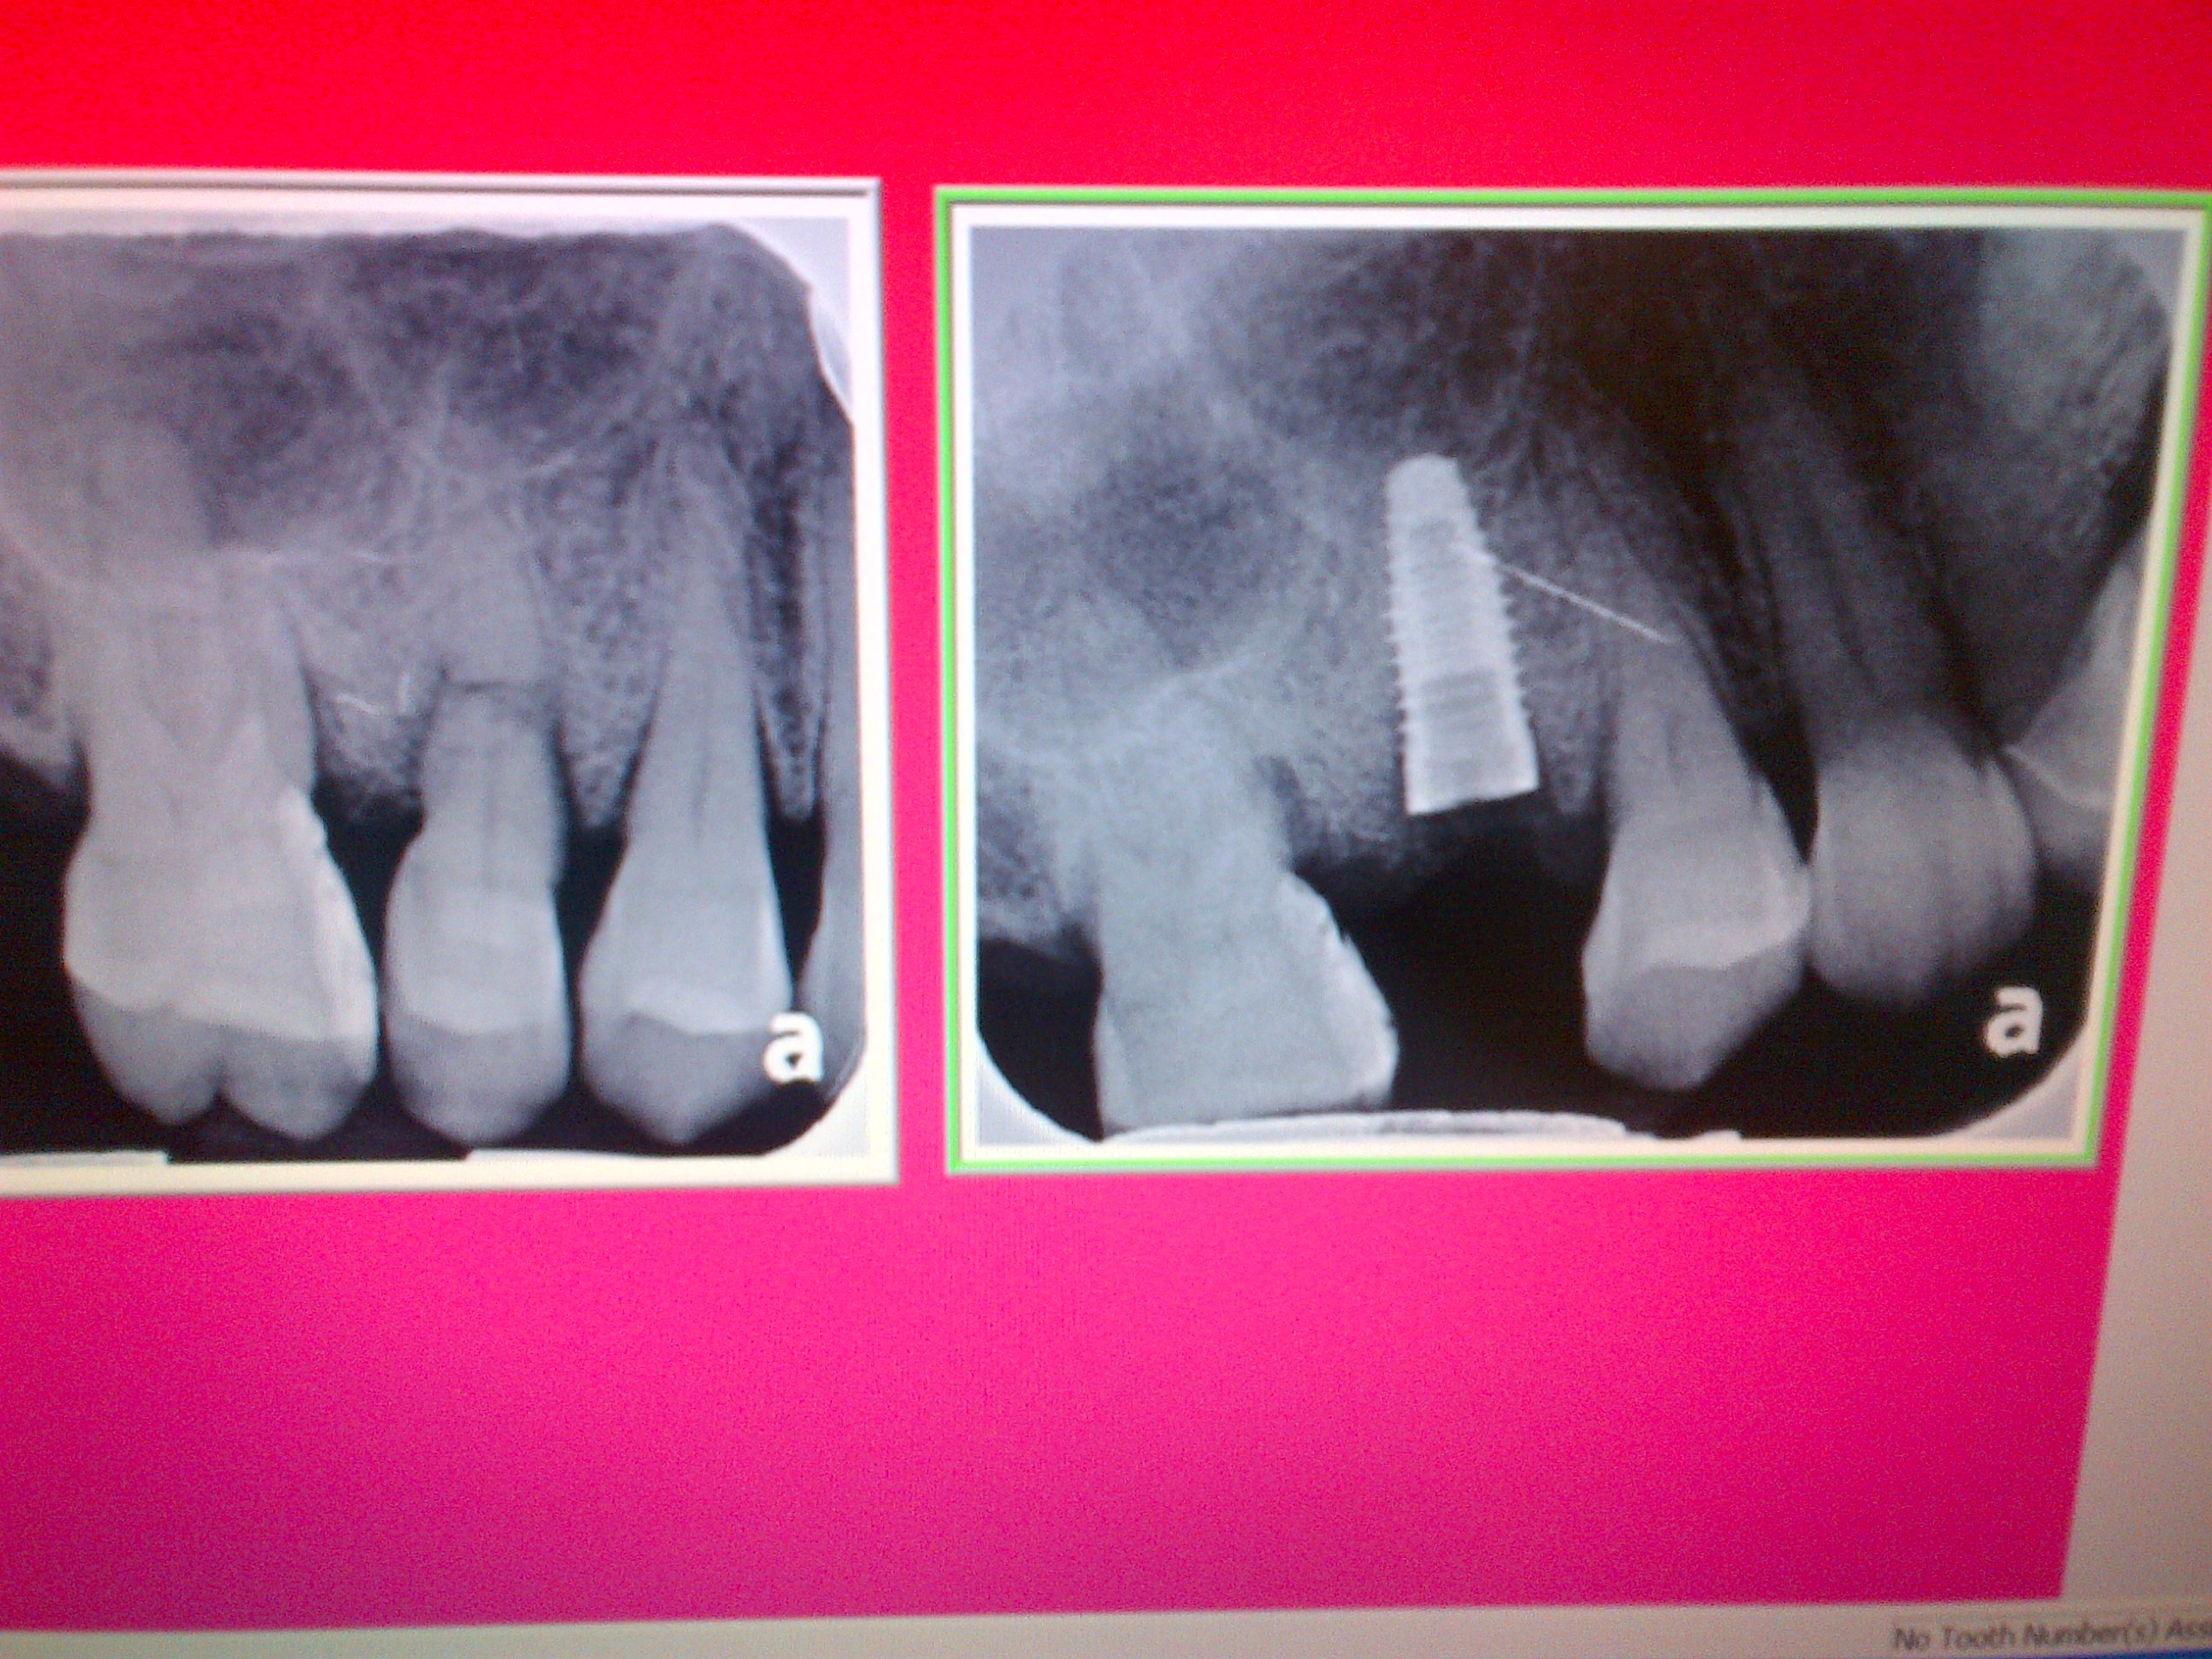

Left photo:  Patient presents as a same day  emergency; post/core crown #7 broken off.

Right photo:  #7 fractured root was extracted, a Nobel Biocare one-piece implant was placed with bone grafting.

The one piece implant allows for an immediate temporary acrylic crown.

Left:  Fractured tooth root - apical 1/3 near sinus     |    Right: Tooth extraction and immediate Implant placement

Horizontal Fractured Root